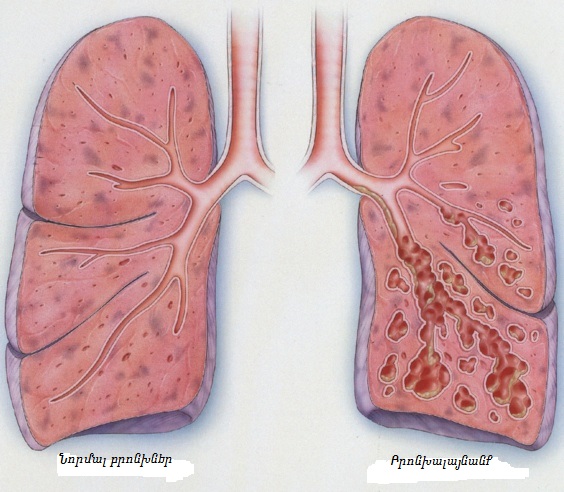

Երևի դժվար թե հանդիպի այնպիսի մարդ, ով իր կյանքի ընթացքում բախված չլինի կրծքային թաց հազի խնդրի։

Երևի դժվար թե հանդիպի այնպիսի մարդ, ով իր կյանքի ընթացքում բախված չլինի կրծքային թաց հազի խնդրի։

Դրա առաջացման պատճառները տարբեր կարող են լինել՝ ծխելուց մինչև բրոնխիտ և թոքաբորբ։